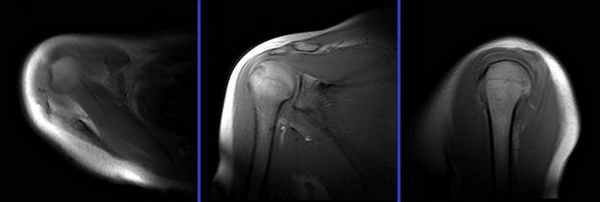

Протоколы нативного МР-исследования и МРА плечевого сустава включали получение трех взаимно перпендикулярных проекций (косой коронарной, косой сагиттальной и аксиальной). Нативное исследование проводилось с использованием следующих импульсных последовательностей: TSE PD SPAIR – изображения, взвешенные по протонной плотности, с эффектом подавления сигнала от жировой ткани; TSE_T1W-Т1 взвешенном изображении (ВИ) в режиме турбо-спин эхо; FFE_T2W-Т2 ВИ в режиме градиентного эхо (табл.1). МРА проводили в режиме TSE_T1W, а также с использования эффекта жироподавления – TSE_T1W SPIR (табл.2, рис.1). Исследование проводилось через 15 минут после введения контраста и выполнения пациентом маятникообразных движений верхней конечностью.

а бРис. 1. МР-артрография. МР-томограммы ПС: а – корональная плоскость, T1 TSE; б,в – аксиальная плоскость T1 TSE, FS T1 TSE